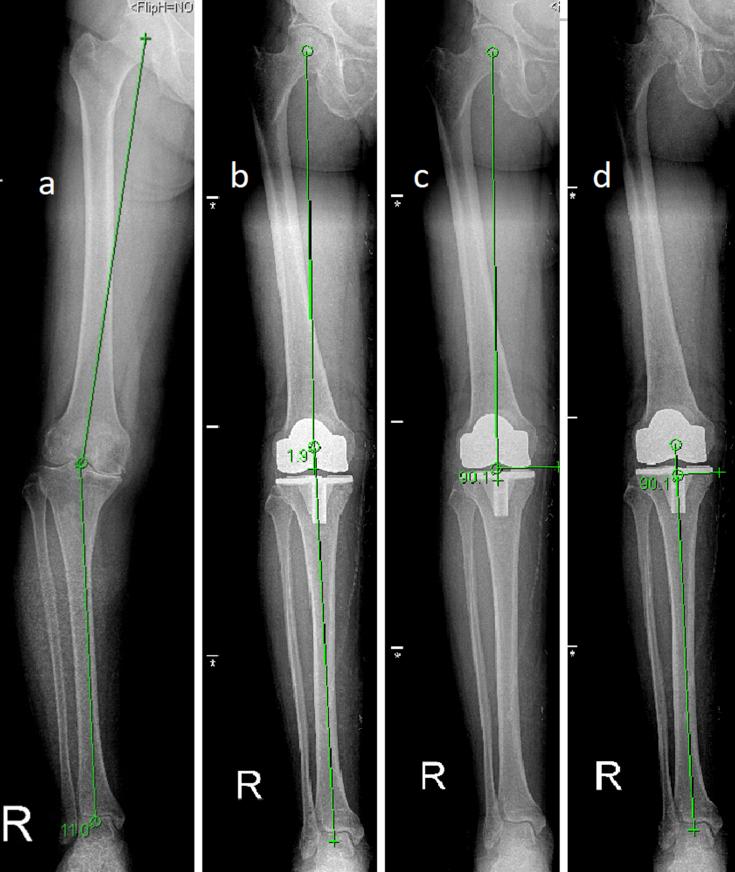

使用3D打印患者特异性器械进行全膝关节置换手术患者的术后机械对线分析:一项前瞻性队列研究。

Postoperative mechanical alignment analysis of total knee replacement patients operated with 3D printed patient specific instruments: A Prospective Cohort Study.

Total knee replacement (TKR) is a surgical treatment for final stage gonarthrosis. The lifespan of the prosthetic implants used in TKR surgery is a major interest for the orthopaedic research community.Previously, proper implant alignment of the implants has been advocated for longevity of the TKR surgery. Recently, patient-specific (PSI) instruments have been proposed to improve the mechanical alignment of the TKR by permitting better implant positioning over conventional TKR surgery. The aim of this study is to compare the mechanical alignment results of patients operated with PSIs and conventional instruments.

METHODS

Two groups of 20 patients chosen in a quasi-random manner have been compared in this study. In the first group femoral distal and tibial osteotomies were made by a PSI which was produced by the patients' computed tomography scans. All osteotomies in the control group were made with the TKR set's routine instruments by conventional means. Patients' preoperative and postoperative mechanical femorotibal angles (mFTA), femoral coronal angles (FCA), tibial coronal angles (TCA) were measured and the number of outliers which showed more than 3° of malalignment were counted in both groups for comparison.

RESULTS

The average postoperative mFTA was found to be 2.09° for the PSI group and in was found to be 2.84° for the control which was not statistically significant. The comparison of postoperative FCA and TCA also did not show significant difference between the groups. The number of outliers showing more than 3° of malalignment per group were found to be 1 out of 20 (5%) for the PSI group and 7 out of 20 (35%) for the control which was statistically significant.

CONCLUSION

In this study patient-specific instrumentation provided significantly better mechanical alignment compared to conventional TKR for the frequency of outlier cases with malalignment beyond 3°. PSI proved no significant difference when the groups were compared for mFTA, FCA and TCA. Our findings support that PSI may improve TKR alignment by improving the ratio of the outlier patients with marked malalignment.

全膝关节置换术(TKR)是终末期膝关节炎的一种外科治疗方法。TKR手术中使用的假体植入物的使用寿命是骨科研究界主要关注的问题。此前,一直提倡通过正确的植入物对线来延长TKR手术的使用寿命。最近,有人提出了患者特异性(PSI)器械,通过在传统TKR手术中实现更好的植入物定位来改善TKR的机械对线。本研究的目的是比较使用PSI器械和传统器械进行手术的患者的机械对线结果。

方法

本研究以准随机方式选取了两组各20例患者进行比较。第一组通过患者的计算机断层扫描生成的PSI进行股骨远端和胫骨截骨。对照组的所有截骨均采用TKR套件的常规器械通过传统方法进行。测量患者术前和术后的机械股胫角(mFTA)、股骨冠状角(FCA)、胫骨冠状角(TCA),并统计两组中显示对线不良超过3°的异常值数量进行比较。

结果

PSI组术后平均mFTA为2.09°,对照组为2.84°,差异无统计学意义。术后FCA和TCA的比较在两组之间也未显示出显著差异。PSI组中显示对线不良超过3°的异常值数量为20例中的1例(5%),对照组为20例中的7例(35%),差异有统计学意义。

结论

在本研究中,与传统TKR相比,患者特异性器械在对线不良超过3°的异常病例发生率方面提供了明显更好的机械对线。当比较两组的mFTA、FCA和TCA时,PSI没有显示出显著差异。我们的研究结果支持,PSI可能通过改善明显对线不良的异常患者比例来改善TKR对线。